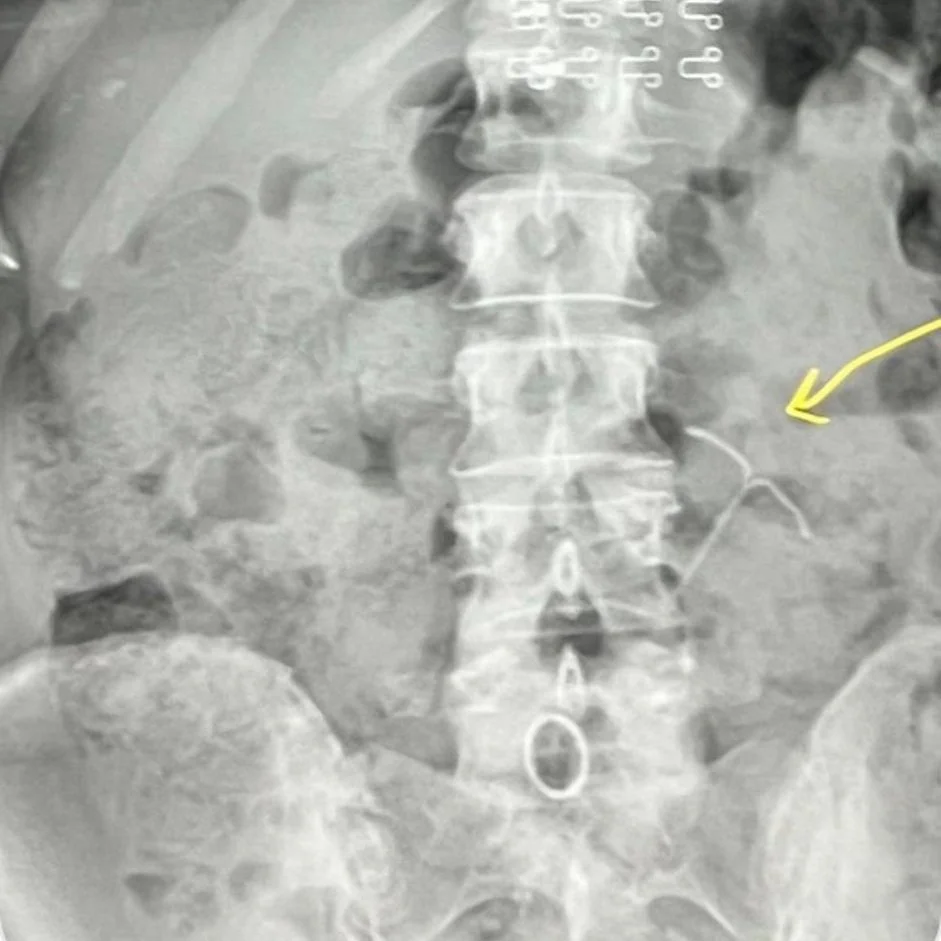

Sometimes an IUD can slip out of place or you could experience embedding or expulsion, which is when the IUD slips out of the uterus partially or completely. In some cases, an IUD can push through the wall of the uterus, however, that is extremely rare.

I spoke with Dr. Hodon Mohamed (that's Dr. Hodon, to her friends), a board-certified OB/GYN and a woman, about IUD movement."ACOG (the American College of Obstetricians & Gynecologists) states that out of every 1,000 IUD insertions there is one that can have the complication of uterine perforation. This is when the IUD moves out the uterus (womb) and is traveling in your abdomen," she says.”